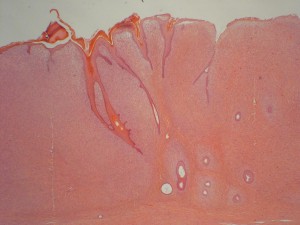

Cette prolifération mésenchymateuse est généralement associée à une hyperplasie non tumorale de l’épiderme (photo 2).

Photo 2 : Sarcoide équin (x10, H&E), prolifération fibroblastique tumorale dans le derme associée à une hyperplasie de l’épiderme sous forme de spicules.

Les fibroblastes tumoraux à la jonction dermo-épidermique sont typiquement arrangés perpendiculairement à l’épiderme (photo 3) et forment plus en profondeur dans le tissu cutané des faisceaux parallèles, tourbillonnants ou enchevêtrés (photo 4).